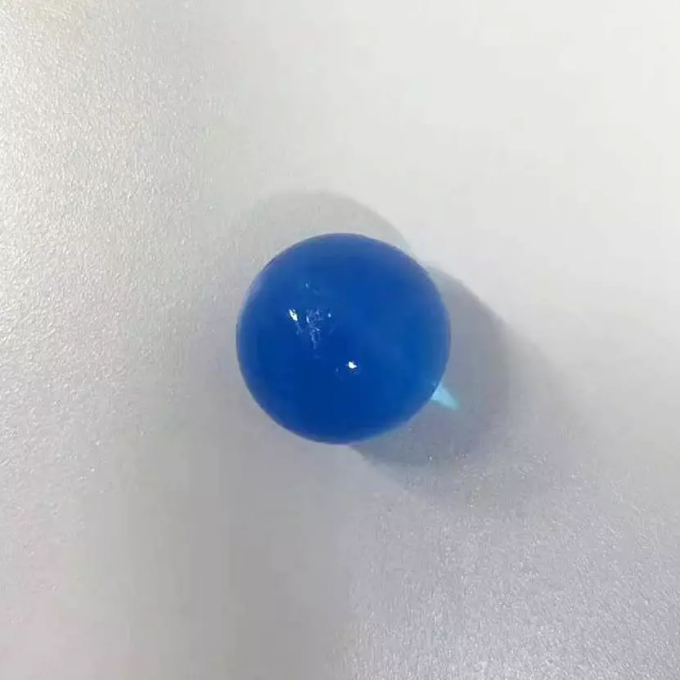

进镜后于胃底体交界处可见一蓝色圆形异物(泡大珠),此时泡大珠已膨胀至1.5cm×1.5cm,脆性增加,为防止在取出过程中泡大珠碎裂,不能完整取出可能会对患儿身体造成二次伤害,术中使用了一次性网兜套圈,完整将异物套住,顺利取出。术后,再次观察泡大珠完整,患儿无不适。

“水精灵”又称海洋宝宝、泡大珠、吸水弹,原本应用于盆栽保水、室内装饰等。它的本质是一种圆珠形吸水树脂(主要成分为丙烯腈、丙烯酸酯)。两者均有一定毒性,对儿童的皮肤和呼吸道有害。因其颜色鲜艳价格低廉,在水中浸泡五六个小时后能“长大”百倍,捏起来软软的还有弹性,近年来被不少黑心商家包装后当作玩具售卖,多为“三无”产品,深受儿童喜欢。